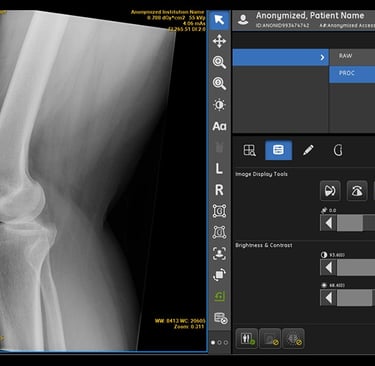

Beyond image interpretation, AI also helps streamline workflows within radiology departments. Radiologists often face high workloads, and AI can assist in tasks like image triaging, where images are automatically categorized based on urgency, allowing radiologists to prioritize critical cases. AI can also support routine image enhancement, ensuring that the quality of X-ray images is optimal for diagnosis.

Image Preprocessing: AI tools can enhance X-ray images by removing noise and adjusting contrast, helping radiologists make more accurate interpretations.